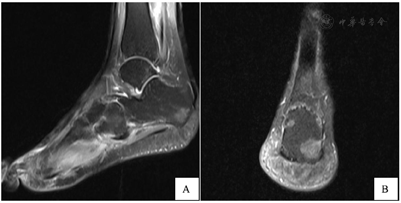

入院后检查:血常规、炎症三项、电解质六项、肝功能、肾功能、血脂、凝血功能、粪便常规、尿常规、女性肿瘤标志物、输血前四项等未见明显异常。左足MR平扫提示(图1):各跗骨及左跟骨结节骨质水肿信号,结合病史,考虑骨髓炎改变;左足底腱膜近跟骨附着处异常信号、足底软组织异常信号,考虑为炎症可能性大,请结合临床。